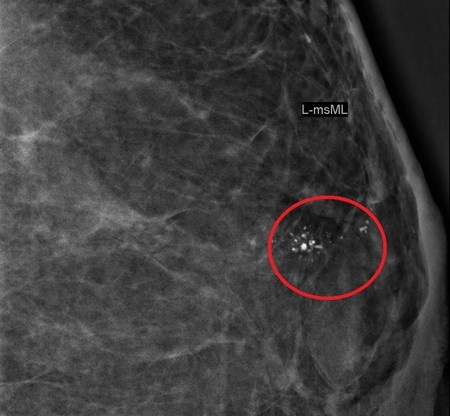

钙化点3种情况 有恶性疑虑

如果医生判定为良性钙化点,定期复查即可。但如果钙化点有以下3种情况,就要小心可能是恶性钙化点:

1. 钙化点成簇聚集,集中在局部乳腺。

2. 不规则外形,例如分岔状、线形、 棒状、多角形等。

3. 钙化点周边乳房组织密度有变化。

如果怀疑乳房钙化点有恶性疑虑,会建议接受组织切片取样。组织切片取样是利用立体定位切片手术来进行,只会在身上遗留一个0.2公分的小伤口,几乎看不太到;待病理诊断结果出炉后,再判断后续的处理方式。